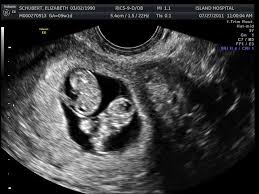

How Big Is My Uterus At 8 Weeks Pregnant With Twins - Symptoms of twin pregnancy at 8 weeks.

How Big Is My Uterus At 8 Weeks Pregnant With Twins - Symptoms of twin pregnancy at 8 weeks.. During pregnancy at term, the uterus measures 38cm in length and 24 to 26cm in width. After attaining puberty, the length is between 5 and 8cm, width is 3.5cm, and thickness is between 1.5 and 3cm. They spend their last few weeks building fat layers and putting on weight. It is scary, though, especially when you think if the end. Besides 8 weeks pregnant showing, your belly will go through a lot of changes during pregnancy.

Their lungs are well developed by 34 weeks. How big should twins be at 8 weeks? What are the symptoms of pregnancy at 8 weeks? Before attaining puberty, the length of the uterus is about 3.5cm and thickness is approximately 1.4cm (7). The signs of having twins or triplets at 8 weeks get very prominent, and you can even celebrate them at the completion of two months if you haven't done so. What are the symptoms of twin pregnancy at 18 weeks? Twin pregnancy symptoms and conditions. After attaining puberty, the length is between 5 and 8cm, width is 3.5cm, and thickness is between 1.5 and 3cm.

They spend their last few weeks building fat layers and putting on weight. Sep 12, 2018 · along with morning sickness, your body will now show some more signs of pregnancy. The average gestational age for twins at birth is 36 weeks. Jan 13, 2019 · symptoms at 8 weeks pregnant with twins. The signs of having twins or triplets at 8 weeks get very prominent, and you can even celebrate them at the completion of two months if you haven't done so. After attaining puberty, the length is between 5 and 8cm, width is 3.5cm, and thickness is between 1.5 and 3cm. Sep 15, 2020 · 36 weeks: Their lungs are well developed by 34 weeks. How big should your belly be at 8 weeks pregnant? It is all based on singleton pregnancies. You feel round ligament pain as pain or tenderness in your abdomen. At this point, your uterus will be visible above your waistline. Your pregnancy symptoms and your twins' development.